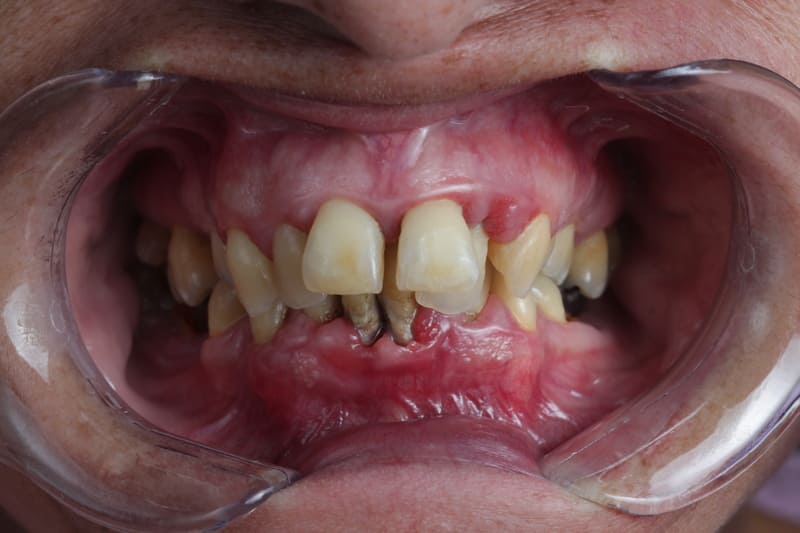

Realizamos un análisis exhaustivo de tu salud bucal, considerando la forma en que muerdes, la alineación de tus dientes, la condición de tus dientes y encías, así como cualquier aspecto estético que desees mejorar.

Realizamos un chequeo detallado que incluye la medición de la profundidad de los sacos alrededor de los dientes, revisamos la inflamación y evaluamos la salud de los tejidos que sostienen tus dientes.